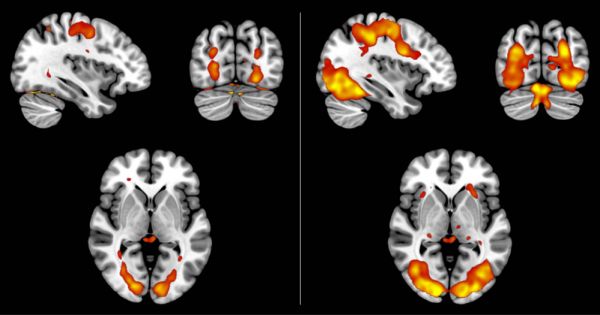

为了深入理解大脑,区分现实与想象的内在机制,研究人员重新分析了此前一项脑部扫描的研究数据,其中35名被试对各种图像,如浇水壶和公鸡等,进行了生动的想象和真实的感知。他们的发现与其他研究结果相符,即在两种情形下视觉皮层中的活动模式极其相似。戴克斯特拉指出:“生动的想象更接近于感知,但模糊的感知是否更近似于想象,这一点我们还不清楚。”有迹象表明,观看模糊图像可能会产生类似于想象的模式,但差异并不显著,这一现象仍需进一步的研究。

扫描结果显示,无论是想象的还是感知的图像,都触发了类似的大脑活动模式,但是对于想象中的图像(图左),信号相对较弱。Nadine Dijkstra